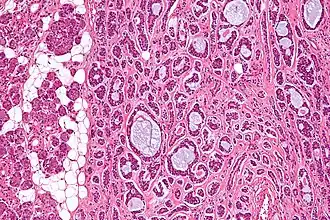

Description de cette image, également commentée ci-après

Aspect en microscopie optique.

Un carcinome adénoïde kystique, ou cylindrome, est un cancer de la famille des adénocarcinomes, le plus souvent développé aux dépens des glandes salivaires, mais aussi de la trachée ou du canal lacrymal.